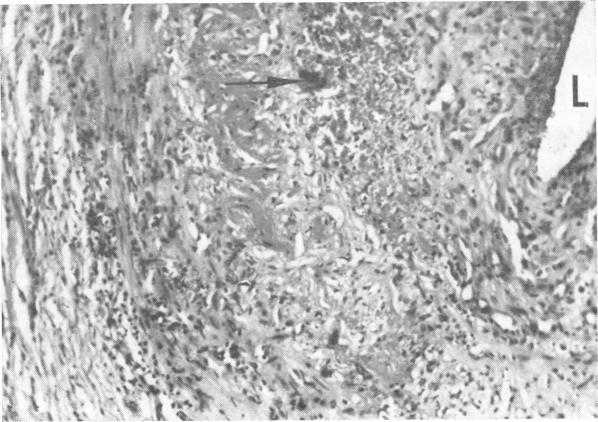

Electron microscopy of giant-cell (temporal) arteritis.

J Neurol Neurosurg Psychiatry. 1969 Aug;32(4):348-53. doi: 10.1136/jnnp.32.4.348.